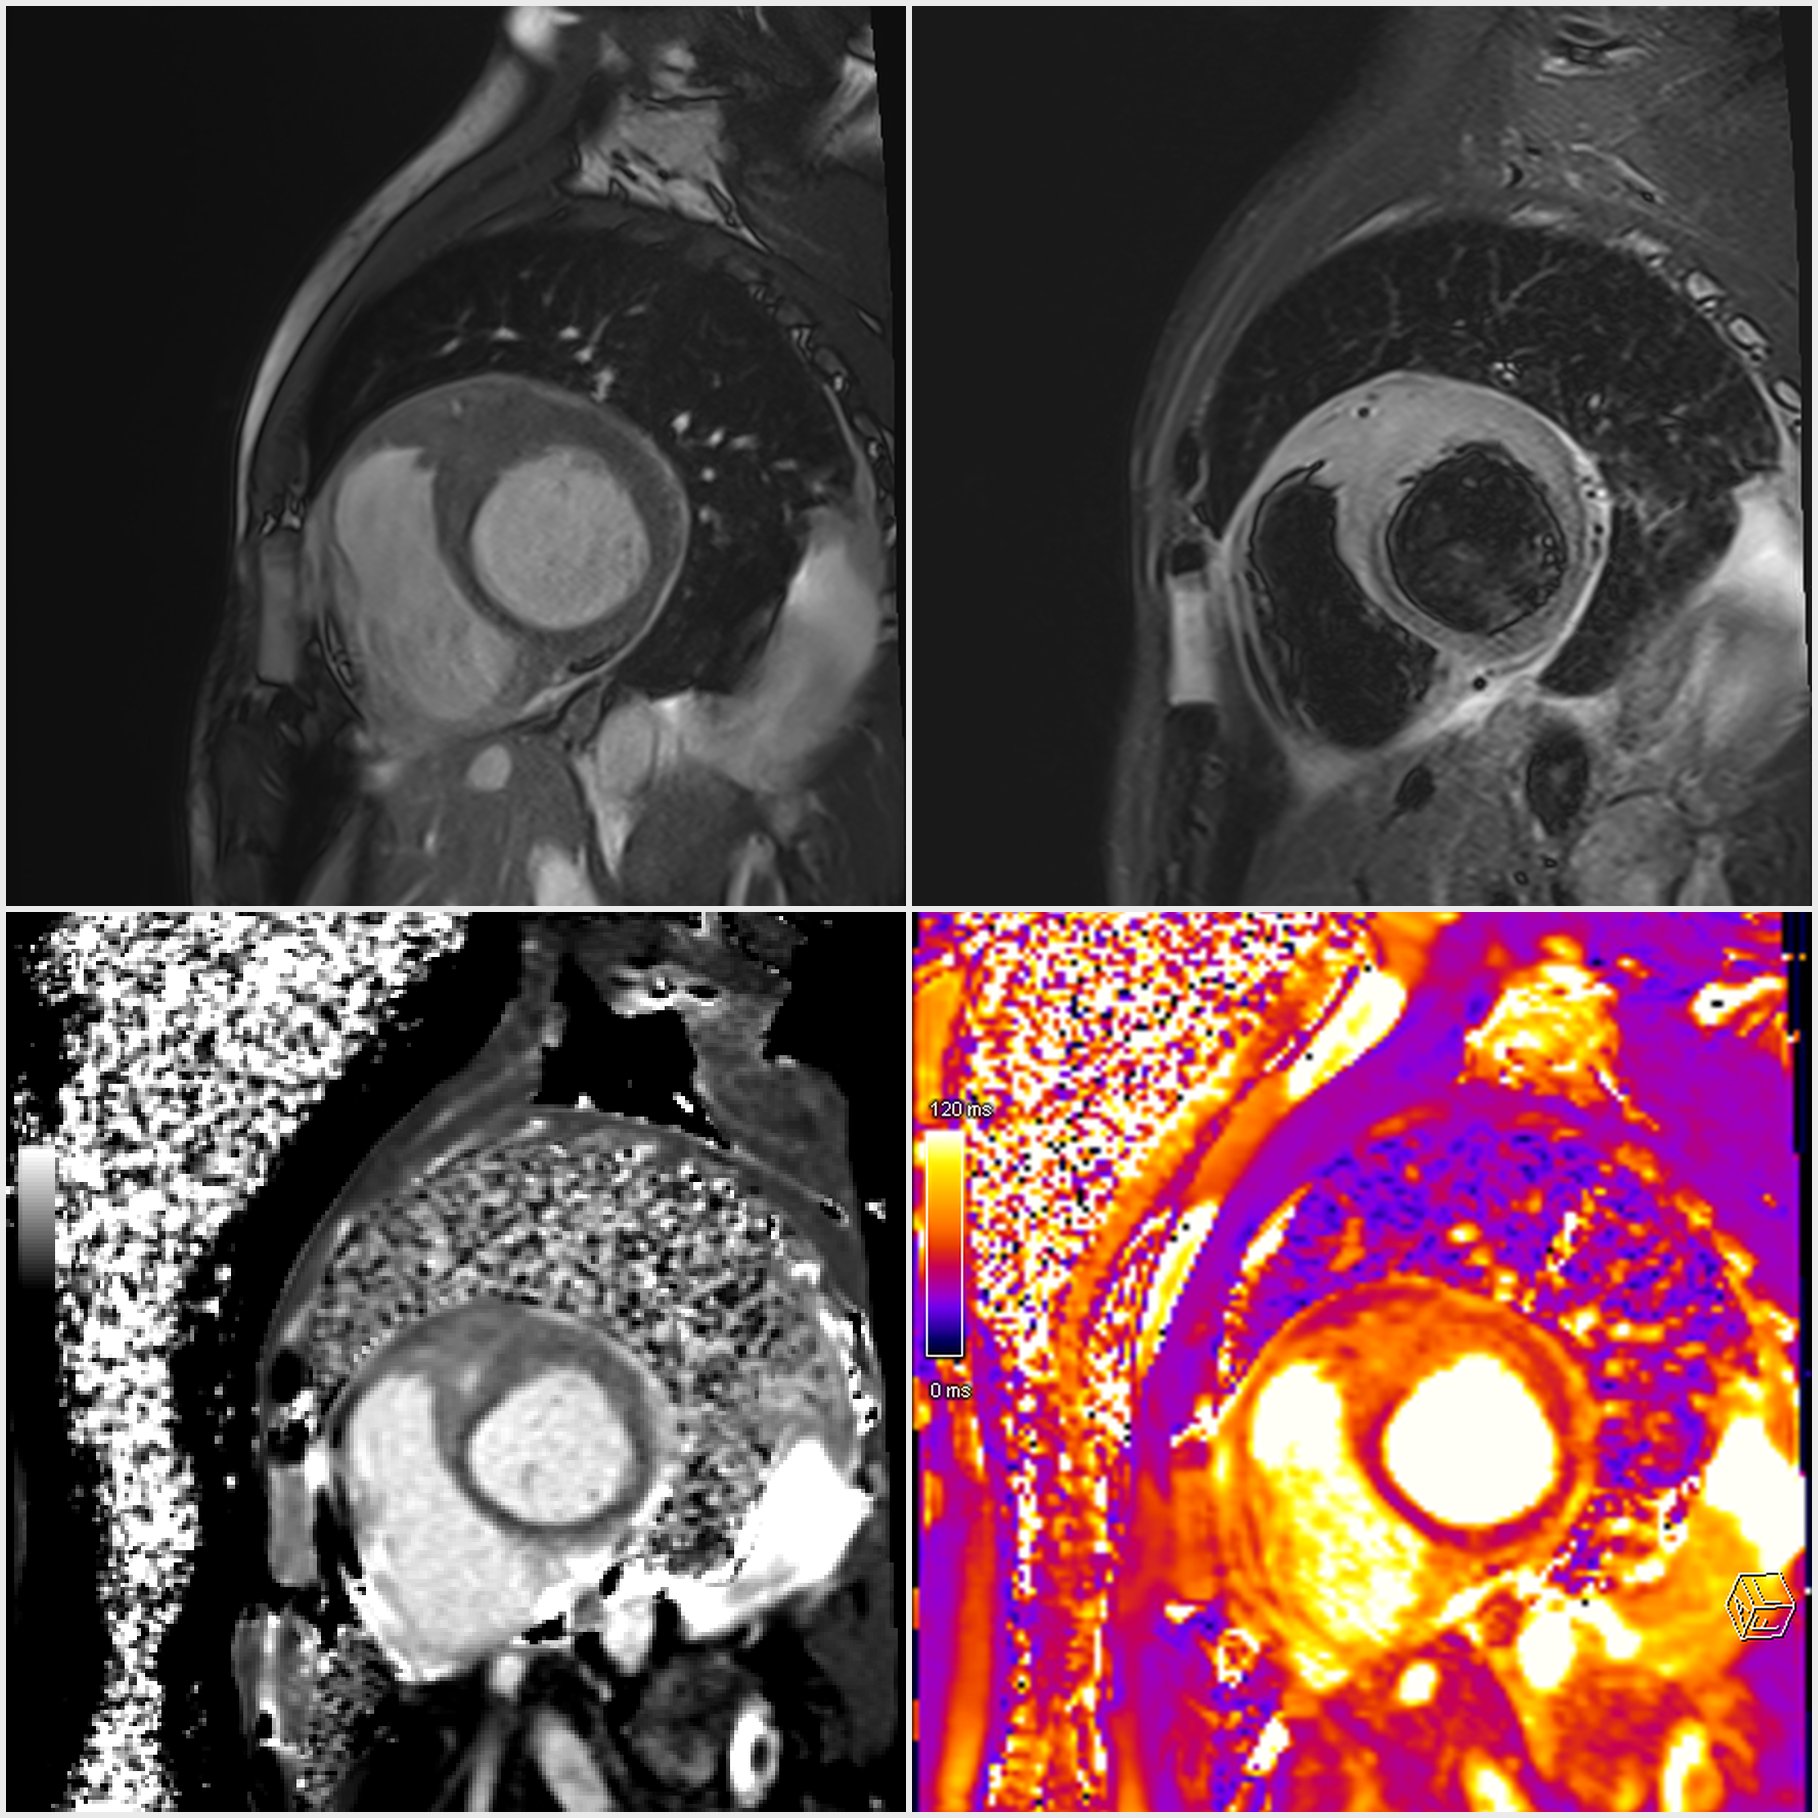

Background: Cardiac involvement in hematologic malignancies is uncommon and often subclinical; it may present with pericardial effusion and myo-pericardial infiltration. Case presentation: A 41-year-old man with relapsed acute lymphoblastic leukemia (prior chemotherapy and two bone-marrow transplant attempts) was referred for hypotension and marked asthenia. He denied chest pain, palpitations, and syncope. ECG showed sinus rhythm, anterior T-wave inversion, and low QRS voltages. Laboratory tests revealed mild anemia and leukocytosis. Urgent echocardiography demonstrated a large circumferential pericardial effusion with pre-tamponade signs (right atrial collapse, marked respiratory variation of transtricuspid inflow) and a dilated, poorly collapsible inferior vena cava; biventricular function was otherwise preserved. Diagnostic-therapeutic pericardiocentesis drained >1,000 mL of frankly hemorrhagic fluid; cytology was positive for malignant cells. CMR showed mid-basal LV wall thickening (anterior/anteroseptal/inferoseptal) with mild T2-STIR hyperintensity and increased T1/T2 mapping values, consistent with myo-pericardial leukemic involvement. Infiltrating tissue was detected along the anterior interventricular groove encasing the left main and LAD, extending to the left atrial anterior/lateral walls and surrounding the circumflex, and reaching the aorto-pulmonary window in close contiguity with the main pulmonary artery; ventricular function was preserved. Speckle-tracking echocardiography showed normal global longitudinal strain with regional reduction in basal anterior, anterolateral, inferolateral segments and basal inferior septum. During ongoing hemato-oncologic therapy, the patient has remained asymptomatic, without recurrent pericardial effusion and with stable echocardiographic parameters. Discussion/Conclusions: A hemorrhagic pericardial effusion with positive cytology may be the first clue of cardio-pericardial infiltration. Regional strain abnormalities can support escalation to advanced imaging; CMR is pivotal for non-invasive tissue characterization and diagnostic confirmation.